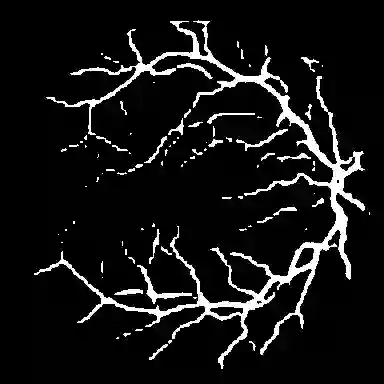

Foundation segmentation models such as the Segment Anything Model (SAM) exhibit strong zero-shot generalization through large-scale pretraining, but adapting them to domain-specific semantic segmentation remains challenging, particularly for thin structures (e.g., retinal vessels) and noisy modalities (e.g., SAR imagery). Full fine-tuning is computationally expensive and risks catastrophic forgetting. We propose \textbf{TopoLoRA-SAM}, a topology-aware and parameter-efficient adaptation framework for binary semantic segmentation. TopoLoRA-SAM injects Low-Rank Adaptation (LoRA) into the frozen ViT encoder, augmented with a lightweight spatial convolutional adapter and optional topology-aware supervision via differentiable clDice. We evaluate our approach on five benchmarks spanning retinal vessel segmentation (DRIVE, STARE, CHASE\_DB1), polyp segmentation (Kvasir-SEG), and SAR sea/land segmentation (SL-SSDD), comparing against U-Net, DeepLabV3+, SegFormer, and Mask2Former. TopoLoRA-SAM achieves the best retina-average Dice and the best overall average Dice across datasets, while training only \textbf{5.2\%} of model parameters ($\sim$4.9M). On the challenging CHASE\_DB1 dataset, our method substantially improves segmentation accuracy and robustness, demonstrating that topology-aware parameter-efficient adaptation can match or exceed fully fine-tuned specialist models. Code is available at : https://github.com/salimkhazem/Seglab.git